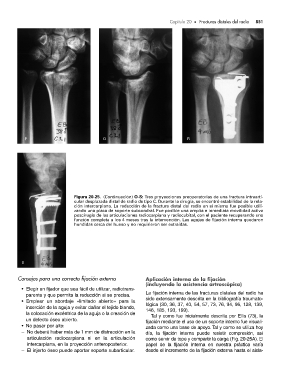

Figura 20-25. (Continuación) O-S: Tres proyecciones preoperatorias de una fractura intraarti-

cular desplazada distal de radio de tipo C. Durante la cirugía, se encontró estabilidad de la rela-

ción intercarpiana. La reducción de la fractura distal del radio en sí misma fue posible utili-

zando una placa de soporte subcondral. Fue posible una amplia e inmediata movilidad activa

poscirugía de las articulaciones radiocarpiana y radiocubital, con el paciente recuperando una

función completa a los 4 meses tras la intervención. Las agujas de fijación interna quedaron

hundidas cerca del hueso y no requirieron ser extraídas.